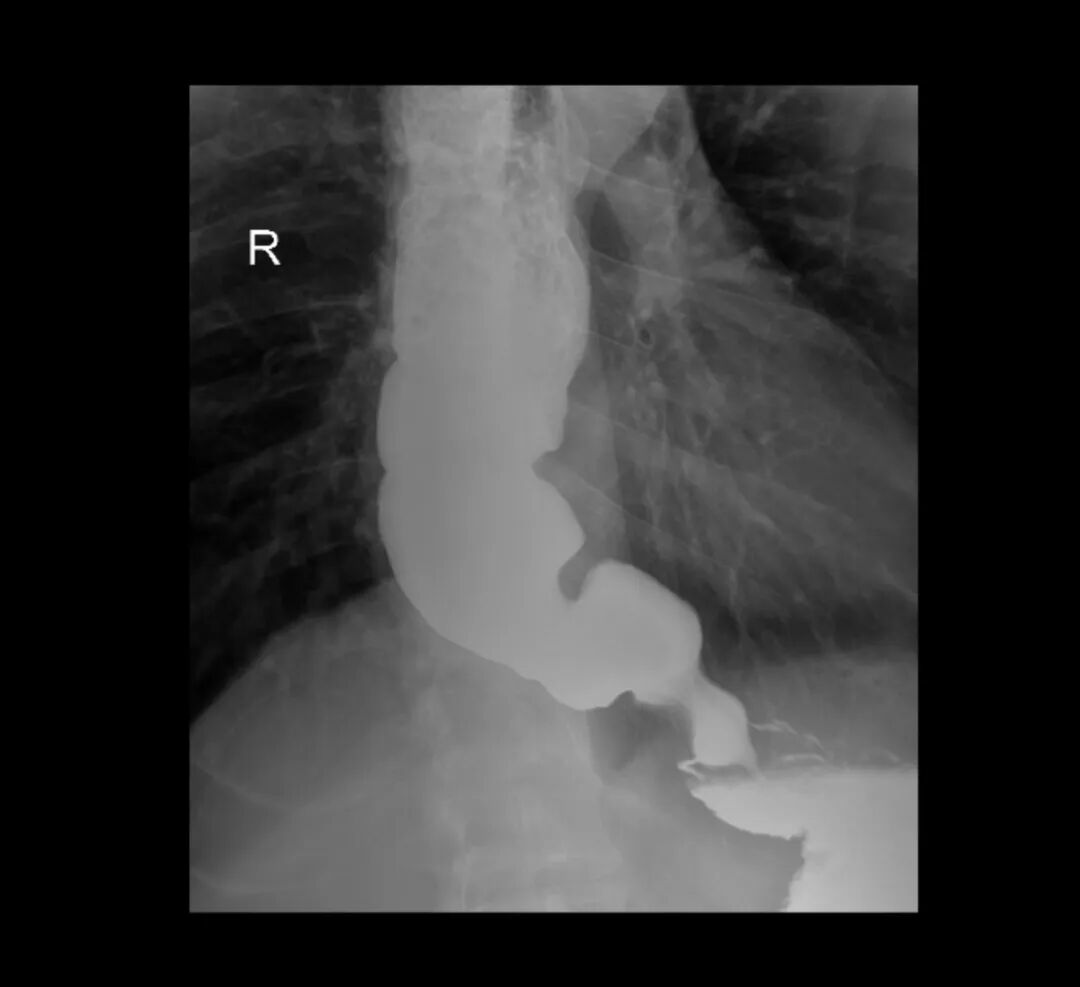

面对复杂的病情,科室团队立刻为他安排了系统检查。食管造影影像清晰地显示:食管中上段扩张明显、下段狭窄呈典型“鸟嘴征”改变;胸部CT提示食管全程扩张,最宽处直径达7cm,最终确诊为贲门失弛缓症。

术前食道造影图